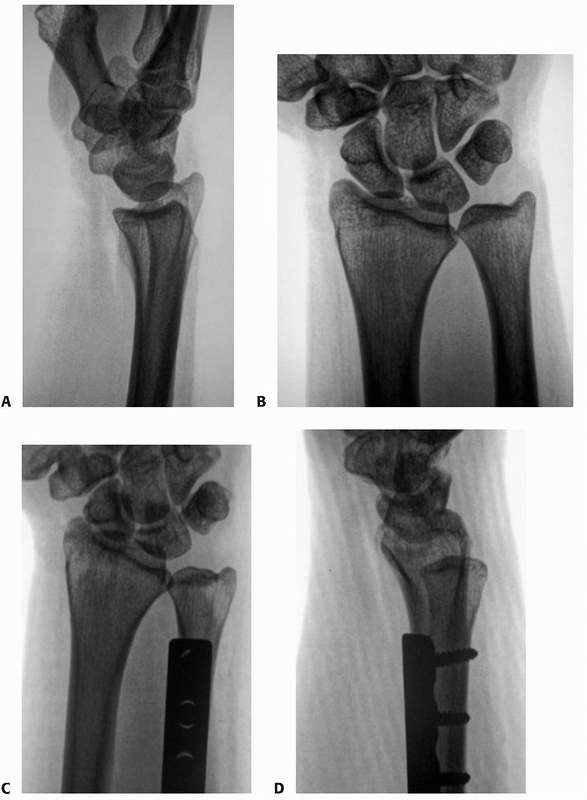

![]() |

FIGURE 30-7 There is incongruity of the radiocarpal joint despite attempted external fixation of the radius (A). The radiographic result (B) is significant arthrosis at 2 years, necessitating a fusion of the wrist.